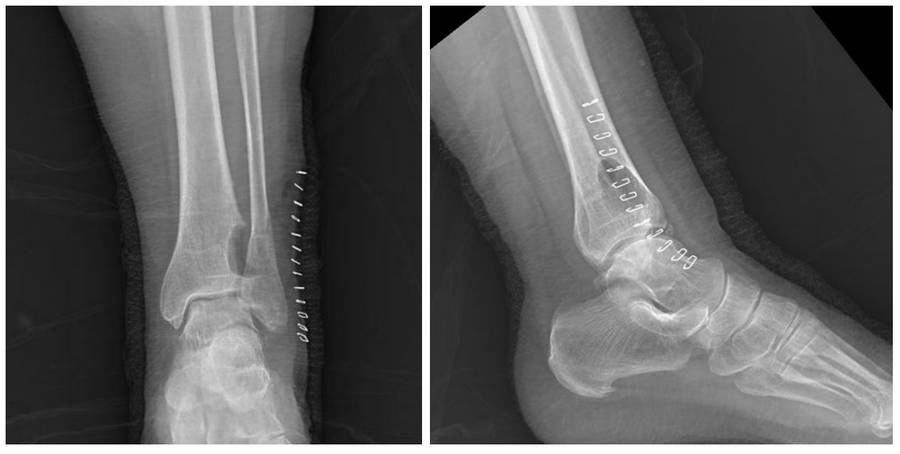

Before the surgery: X-ray shows an irregularly bordered mass in the anterolateral aspect of the distal tibia.

Post-Surgery: The X-ray shows the cavity that formed after the mass was removed.